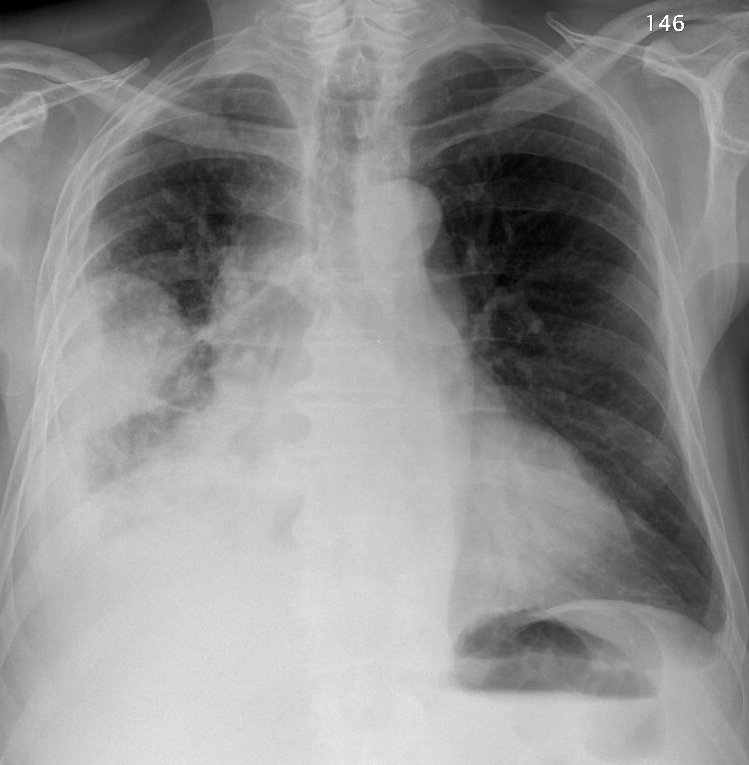

Pleural

mesothelioma PA